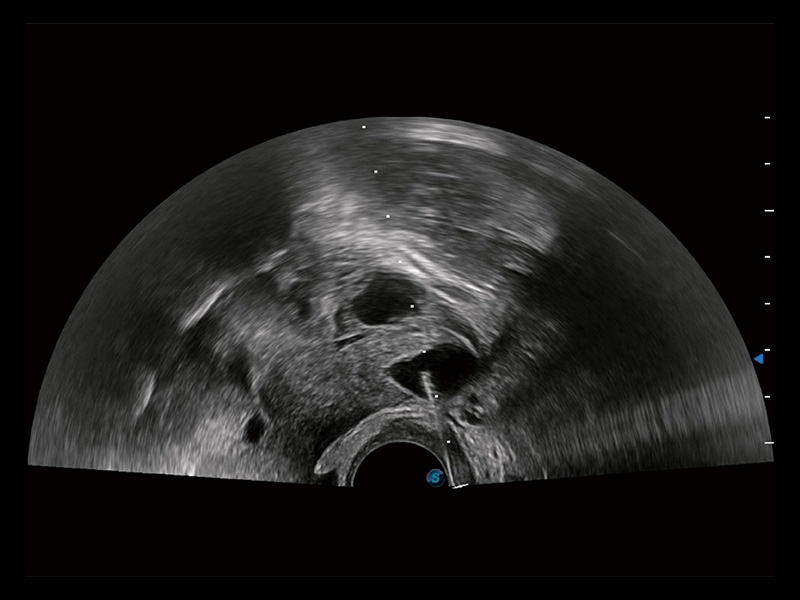

临床图

超声引导下双侧卵巢穿刺取卵